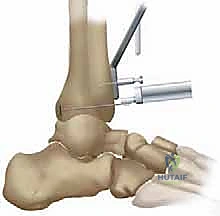

- Lateral Incision and Joint Exposure: Through a separate 2.5-cm lateral incision made directly over the sinus tarsi, we expose the subtalar joint.

- Cartilage Removal: Using a chisel and a curette, we meticulously remove all residual articular cartilage from the subtalar joint surfaces.

- Subchondral Bone Preparation: To facilitate fusion, we use a small diameter drill to penetrate the subchondral bone, creating multiple bleeding points and increasing the surface area for fusion.

- Screw Fixation: Through the primary anterior incision, positioned anterior to the newly implanted talar component, a standard AO cancellous screw is placed from the talar neck, across the subtalar joint, and into the calcaneus. This provides stable compression for fusion.

TECH FIG 5 • Subtalar arthrodesis. A. Postoperative AP view with subtalar arthrodesis using a single OA cancellous screw.

TECH FIG 5 • Subtalar arthrodesis. B. Lateral view.